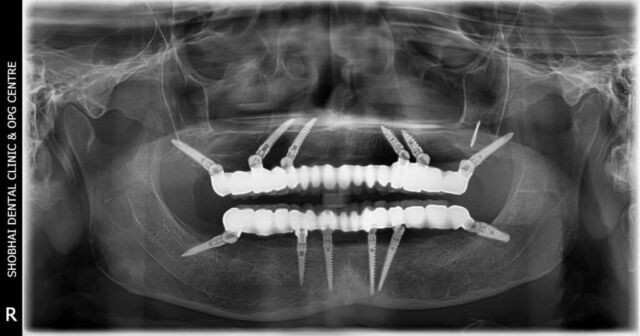

We offer all types of dental treatments at our dental clinic including basic and advanced treatments like full mouth dental implants.